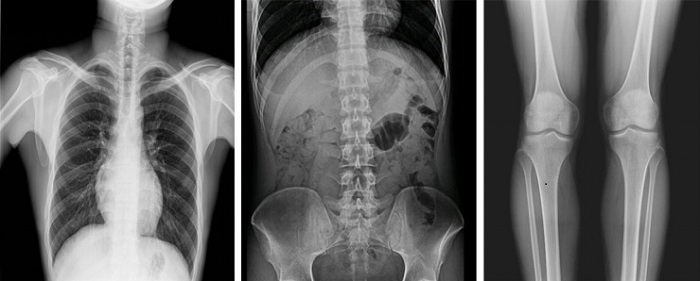

以普利德多功能動態平板DRF為例,一改傳統DR只能進行盲拍的模式,通過多角度動態實時影像實現全方位觀察,當疑似病灶出現時,進行瞬時高清點片,精準捕獲高清病灶圖,大大降低漏診誤診率。同時,17×17英寸大幅面成像,能對胸部、腹部等部位實現大范圍全覆蓋,更便于醫生觀察和診斷。